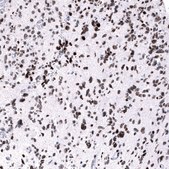

immunofluorescence: 2-10 μg/mL (ICC-IF), immunohistochemistry: 1:500 - 1:1000

The Human Protein Atlas project can be subdivided into three efforts: Human Tissue Atlas, Cancer Atlas, and Human Cell Atlas. The antibodies that have been generated in support of the Tissue and Cancer Atlas projects have been tested by immunohistochemistry against hundreds of normal and disease tissues and through the recent efforts of the Human Cell Atlas project, many have been characterized by immunofluorescence to map the human proteome not only at the tissue level but now at the subcellular level. These images and the collection of this vast data set can be viewed on the Human Protein Atlas (HPA) site by clicking on the Image Gallery link. We also provide Prestige Antibodies® protocols and other useful information.

• IHC tissue array of 44 normal human tissues and 20 of the most common cancer type tissues.